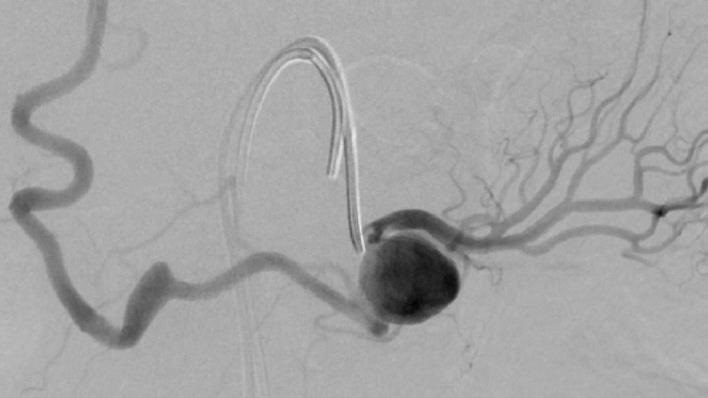

末端动脉栓塞:医源性肾损伤-移植肾活检

活检后动脉瘤破裂 |

微导管在载瘤动脉末端 |

载瘤动脉末端栓塞 |

Coil=3 |